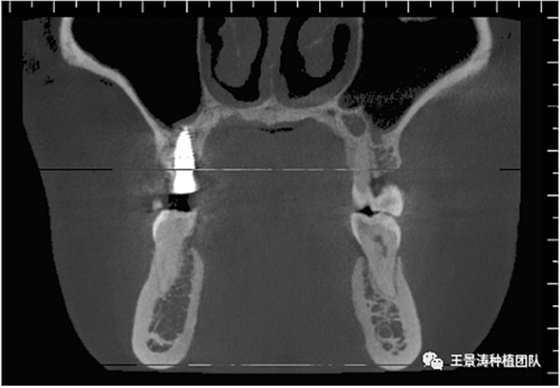

下述病例則是15區(qū)域的即刻種植,15因牙冠折斷于齦下,無法樁核冠修復(fù),則考慮種植修復(fù)。但拍攝CBCT后發(fā)現(xiàn)根尖距上頜竇底距離較短?;颊邽槟贻p女性,無全身系統(tǒng)疾病且可利用上頜竇底與根尖皮質(zhì)骨雙側(cè)皮質(zhì)骨固位,且此位置可通過頰側(cè)軟組織減張技術(shù)獲得嚴(yán)密封閉牙槽窩。因其根尖距上頜竇距離較低,遂拔除15后行上頜竇內(nèi)提升,埋入式種植,最終修復(fù)的完成。

左側(cè)下頜第二磨牙及右側(cè)下頜第一磨牙同時(shí)即刻種植病例?;颊吣贻p女性,無系統(tǒng)性疾病。37及46殘冠及殘根,且46劈裂,無法冠修復(fù),必須拔除。37根尖慢性炎癥,大量肉芽組織存在,46根分叉較高,根分叉骨質(zhì)尚可。CBCT示:根尖骨質(zhì)至下牙槽神經(jīng)管距離可滿足種植體的初期穩(wěn)定性,遂考慮即刻種植,并在種植體周邊填入骨粉并覆蓋骨膜,雙側(cè)的種植體初期穩(wěn)定性相差無幾,但考慮到37根尖慢性炎癥較大,遂給予埋入式種植。

患者左側(cè)16慢性根尖周炎,17缺失。16根尖炎癥距上頜竇底較近,需內(nèi)提升,但是因?yàn)閮?nèi)提升后骨質(zhì)較薄所致植入深度過深,埋入式植入。17非埋入式種植。后期效果均可。